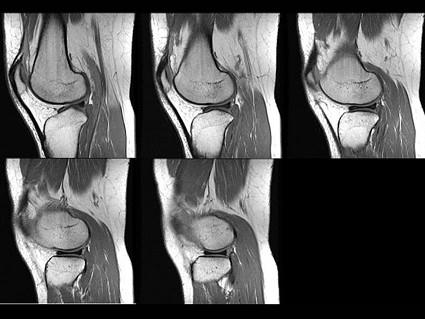

请根据所提供的图像,选择最佳选项是 ( )A、半月板损伤B、半月板囊变C、桶状半月板D、半月板黏液样变E、盘状半月板

问题 请根据所提供的图像,选择最佳选项是 ( )

选项 A、半月板损伤 B、半月板囊变 C、桶状半月板 D、半月板黏液样变 E、盘状半月板

答案 E